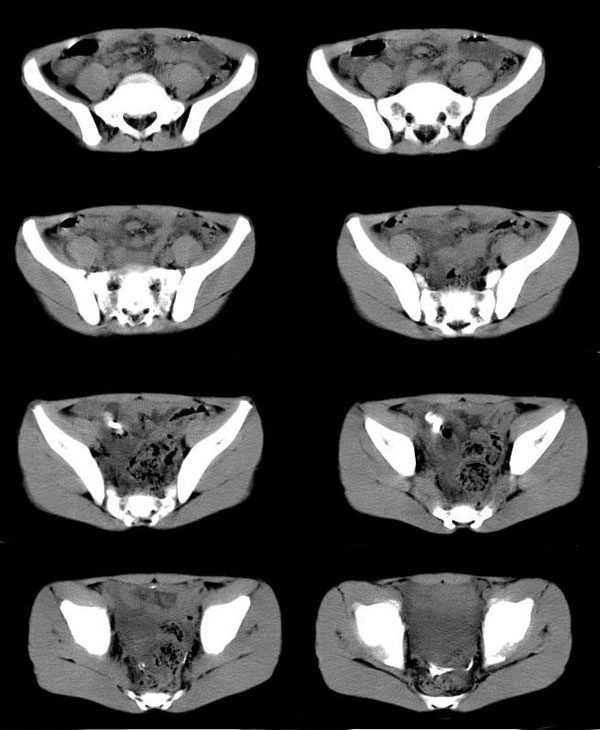

阑尾炎伴钙化,脓肿形成

男孩,9岁.2岁时在北京某大医院确诊为阑尾炎,当时保守治疗,近三天发热,下腹疼,已手术.

手术结果

阑尾炎伴钙化脓肿形成